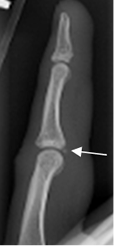

Con la Rx puede apreciarse avulsión de la inserción, en la parte anterior de la falange media o distal. (Fig 66).

Fig 66. Lesión del mecanismo flexor.

Rx lateral. Fragmento óseo desprendido en la parte anterior de la base de la falange media, por avulsión del flexor superficial.